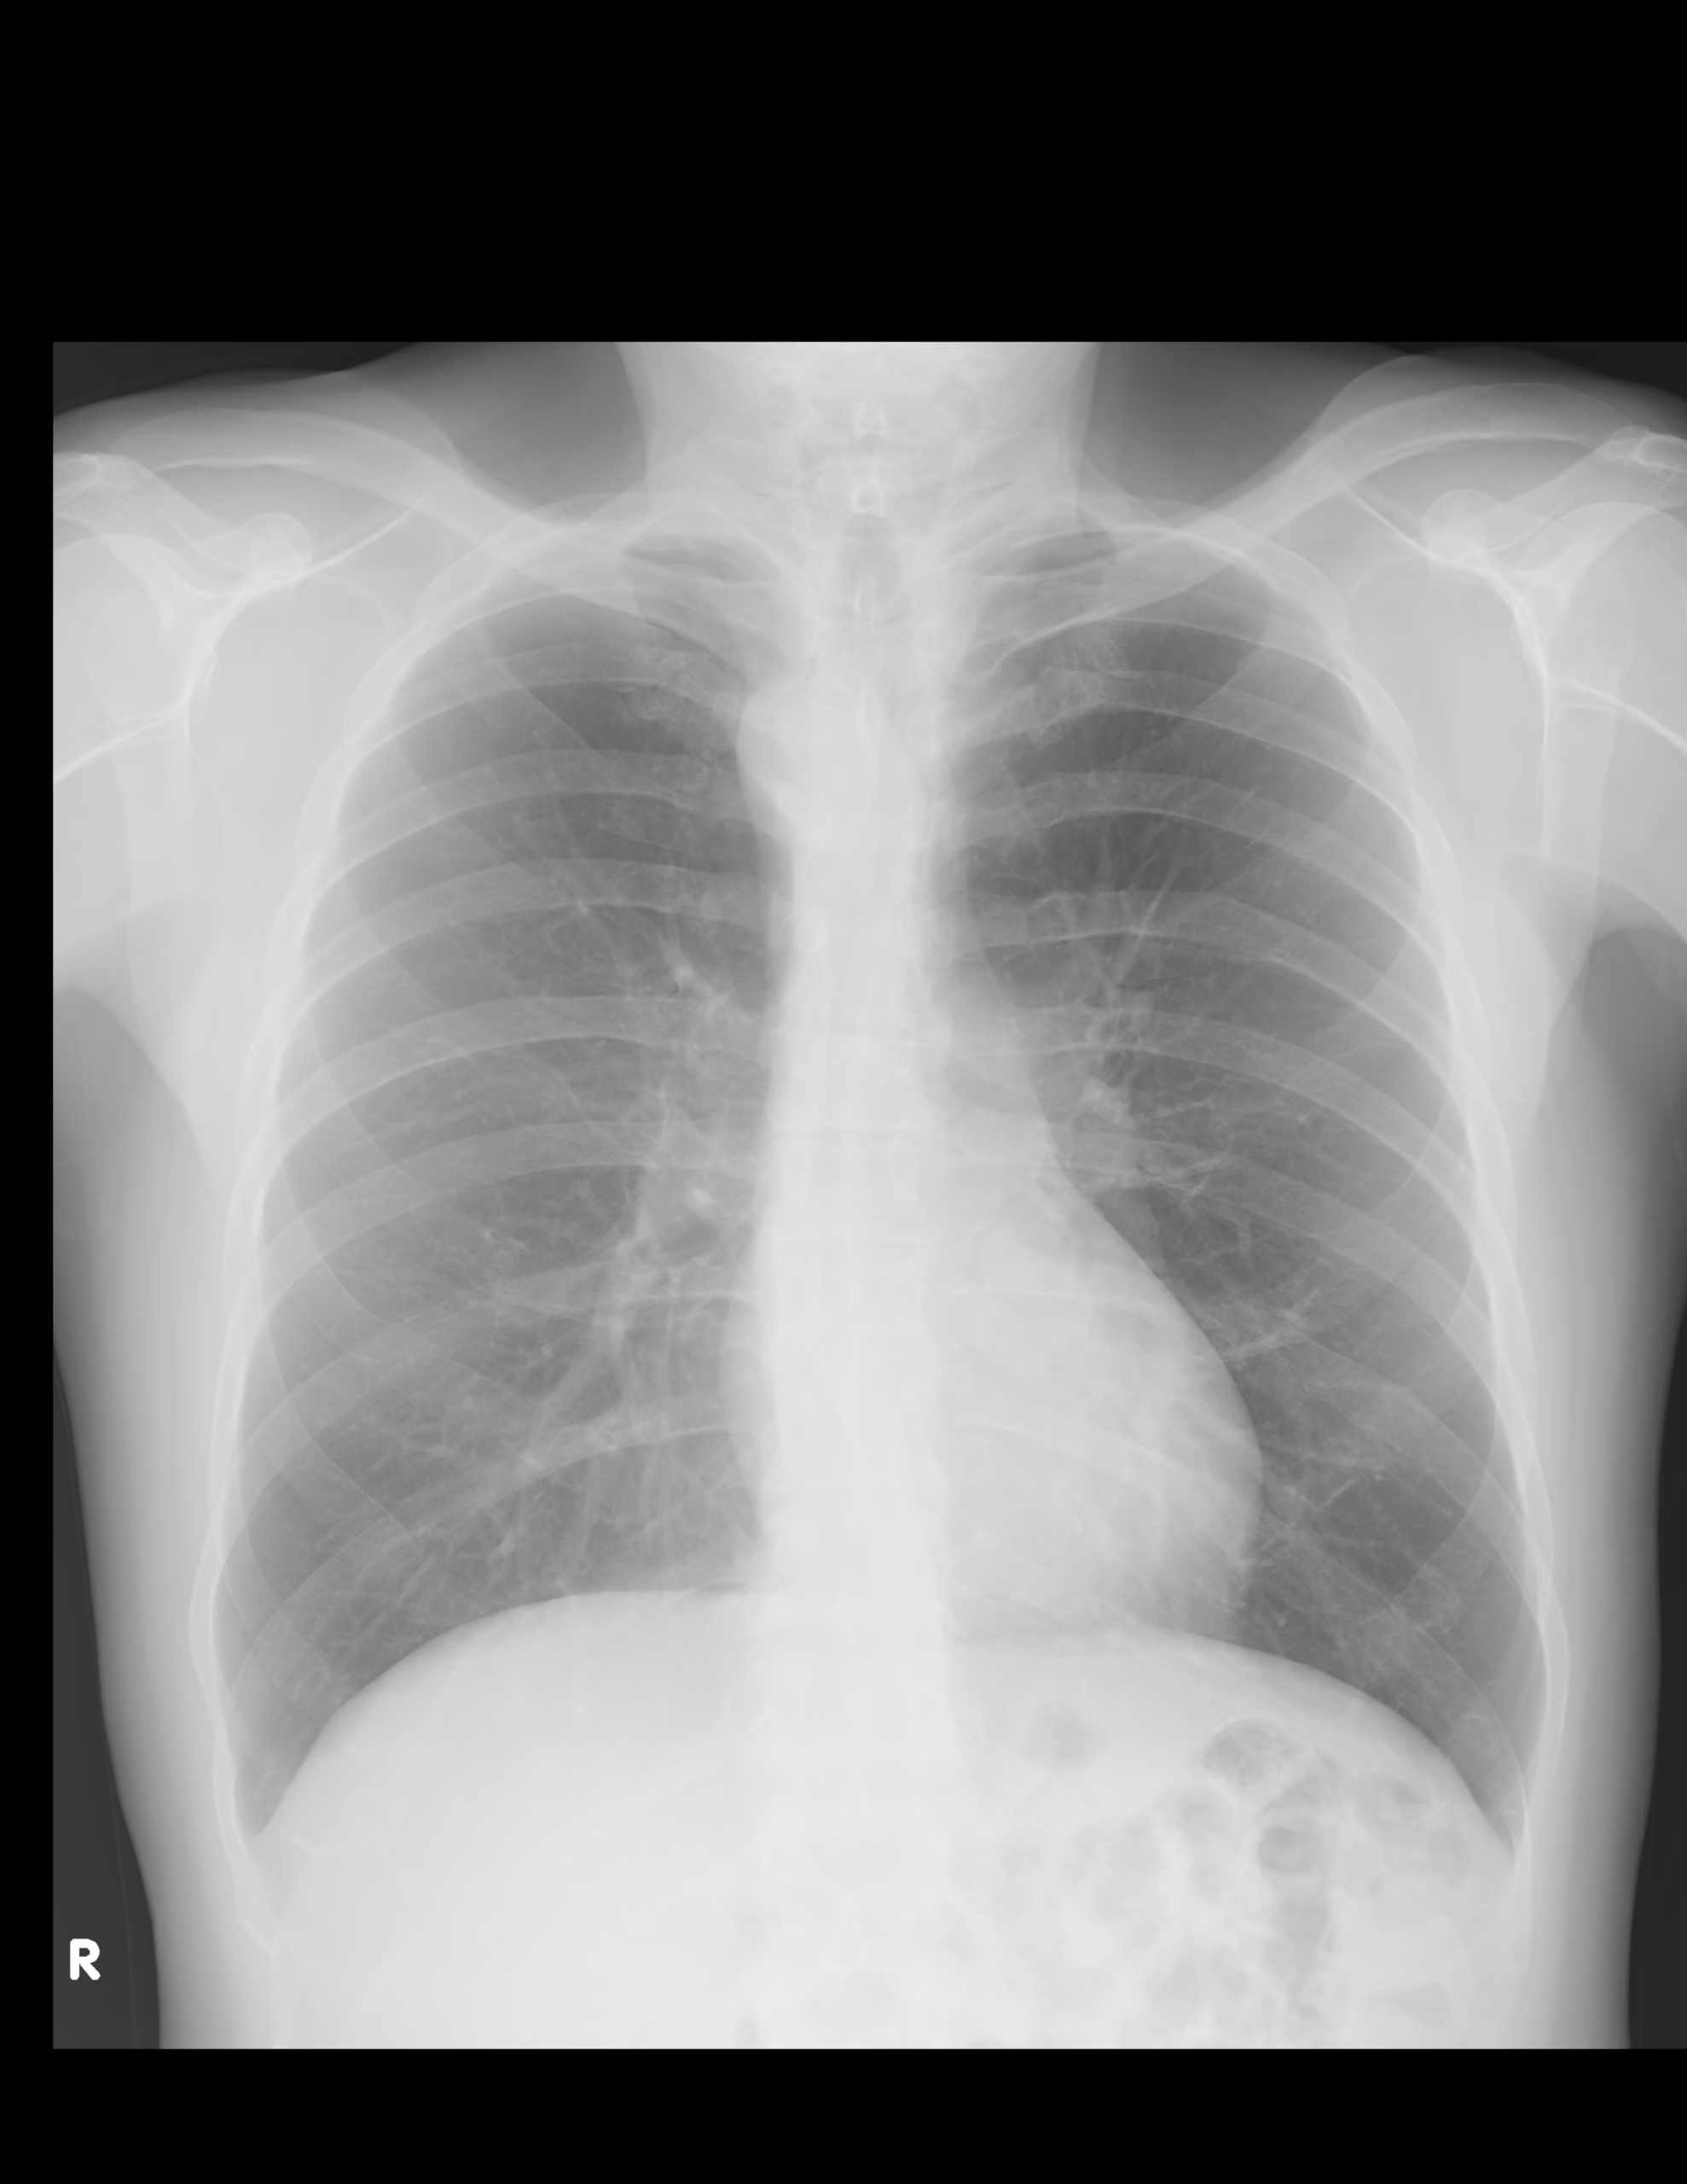

LA PROYECCION RADIOLOGICA OBTENIDA NOS MUESTRA LOS SIGUIENTES HALLAZGOS:

-Tejidos blandos, simétricos, con adecuada densidad, sin evidencia alteraciones.

-Estructuras óseas, sin evidencia de lesiones líticas, blásticas o perdida de la contigüidad. Existen algunos osteofitos marginales

-Vía aérea permeable, central. Botón aórtico sin calcificaciones, con desviación hacia la derecha.

-Mediastino, conservando sus diámetros.

-Corazón, central, con índice cardiotorácico menor a 0.5

-Hilios pulmonares, sin alteraciones.

-Trama bronco-vascular, con adecuado trayecto, densidad y calibre.

-Campos pulmonares, sin evidencia de opacificaciones, nódulos, masas o derrame pleural.

-Recesos costofrénicos y cardiofrénicos se observan sutilmente el signo del menisco de manera bilateral.

OPINIÓN RADIOLÓGICA:

- EN EL PRESENTE ESTUDIO RADIOGRÁFICO, SIN EVIDENCIA DE LESIONES PARENQUIMATOSAS.

- EXISTE APARENTE SIGNO DEL MENISCO DE MANERA BILATERAL, SUGERENTE DE DERRAMÉ PLEURAL BILATERAL ESCASO.

- BOTÓN AÓRTICO, CON DESVIACIÓN HACIA LA DERECHA.

- EXISTEN CAMBIOS OSTEODEGENERATIVOS INCIPIENTES.

- LEER DESCRIPCIÓN Y OTORGAR VALOR DIAGNÓSTICO.

- CORRELACIONAR CON DATOS E HISTORIA CLINICA DEL PACIENTE.